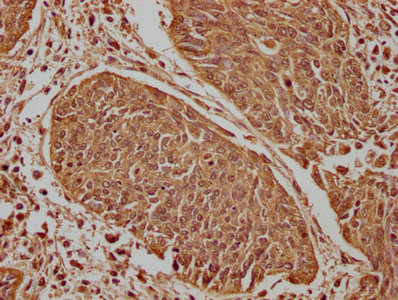

IHC image of CSB-PA666060LA01HU diluted at 1:100 and staining in paraffin-embedded human cervical cancer performed on a Leica BondTM system. After dewaxing and hydration, antigen retrieval was mediated by high pressure in a citrate buffer (pH 6.0). Section was blocked with 10% normal goat serum 30min at RT. Then primary antibody (1% BSA) was incubated at 4°C overnight. The primary is detected by a biotinylated secondary antibody and visualized using an HRP conjugated SP system.